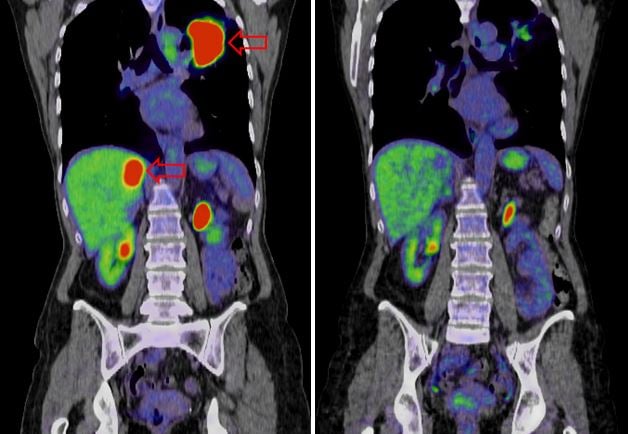

Liver cancer, लिवर कैंसर, जिसे हेपैटोसेलुलर कार्सिनोमा भी कहा जाता है, एक प्रकार का कैंसर है जो लिवर की कोशिकाओं में उत्पन्न होता है। यह एक गंभीर स्थिति है जिसके लिए तत्काल चिकित्सा ध्यान देने की आवश्यकता है। इस लेख में, हम लिवर कैंसर के लक्षण, कारण और उपचार के विकल्पों का पता लगाएंगे।

लिवर कैंसर का इलाज

लिवर कैंसर के उपचार के विकल्प रोग की अवस्था और रोगी के समग्र स्वास्थ्य पर निर्भर करते हैं। निम्नलिखित सामान्य उपचार दृष्टिकोण हैं:

सर्जरी: शुरुआती चरण के लिवर कैंसर के लिए ट्यूमर को सर्जरी से हटाना एक विकल्प हो सकता है।

प्रत्यारोपण: ऐसे मामलों में जहां ट्यूमर को शल्य चिकित्सा द्वारा नहीं हटाया जा सकता है, यकृत प्रत्यारोपण पर विचार किया जा सकता है।

कीमोथेरेपी: कीमोथेरेपी कैंसर कोशिकाओं को मारने या उनकी वृद्धि को धीमा करने के लिए दवाओं का उपयोग करती है। इसे मौखिक या अंतःशिरा द्वारा प्रशासित किया जा सकता है।

विकिरण चिकित्सा: यह उपचार कैंसर कोशिकाओं को लक्षित करने और नष्ट करने के लिए उच्च-ऊर्जा किरणों का उपयोग करता है।

लक्षित चिकित्सा: लक्षित चिकित्सा दवाएं विशेष रूप से कैंसर कोशिकाओं को लक्षित करने और उनकी वृद्धि को रोकने के लिए डिज़ाइन की गई हैं।